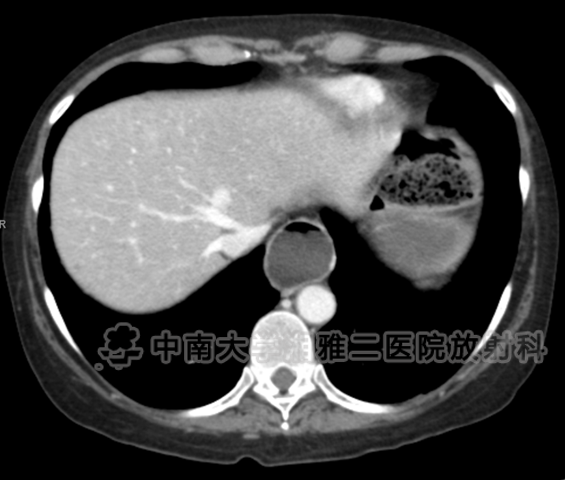

● 对比增强CT显示食管明显扩张(箭头所示)。